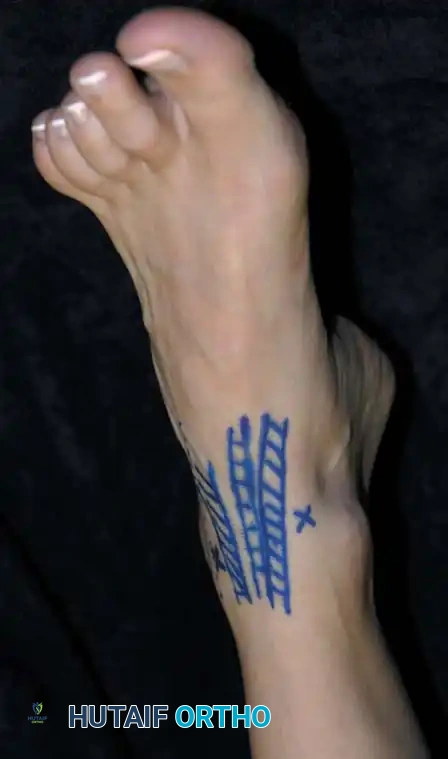

Clinical photograph demonstrating the marking of two anterior portals in relation to the anterior tibial and other extensor tendons.

2. Landmark Identification and Joint Distention

- Elevate the extremity, exsanguinate with an Esmarch bandage, and inflate the tourniquet.

- Carefully outline the bony landmarks: the medial malleolus, lateral malleolus, and the anterior joint line (approximately 2.5 cm proximal to the tip of the lateral malleolus).

- Mark the anticipated anteromedial, anterolateral, and posterolateral portals.

- Insert an 18-gauge spinal needle at the marked anteromedial portal site, directing it toward the anatomic center of the joint.

- Inflate the joint with 20 mL of sterile normal saline. Proper intra-articular placement is confirmed by the visible bulging of the joint capsule medially and laterally, and the easy backflow of fluid through the needle hub.

3. Portal Creation

- Establish the anterolateral portal first. Place a spinal needle at the site and confirm fluid return.

- Use a No. 11 blade to make a vertical 5-mm skin incision. Use a small hemostat to bluntly spread the subcutaneous tissues down to the capsule, protecting the superficial peroneal nerve branches.

- Insert a blunt trocar and cannula through the capsule, directing it toward the center of the joint. Never use a sharp trocar, as it can easily scuff the highly congruent talar articular surface.